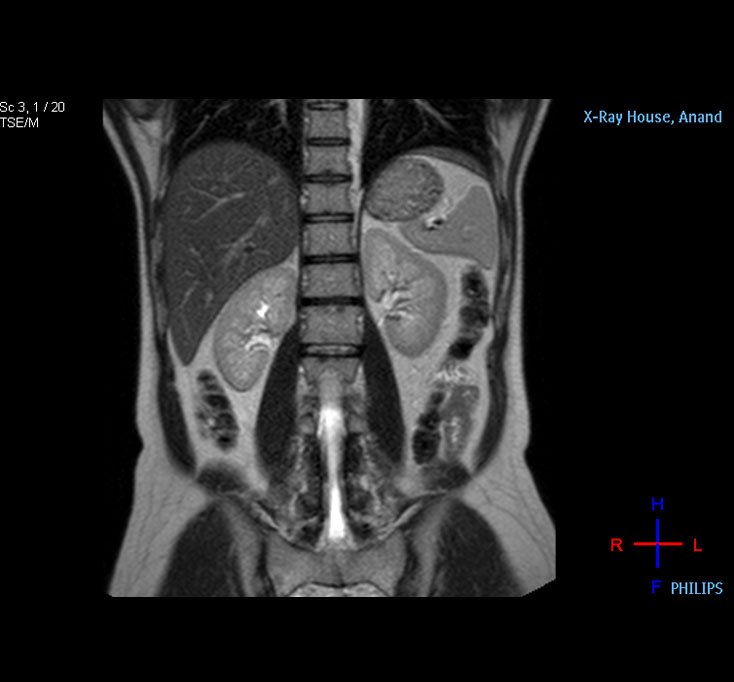

Kidney MRI

Liver MRI